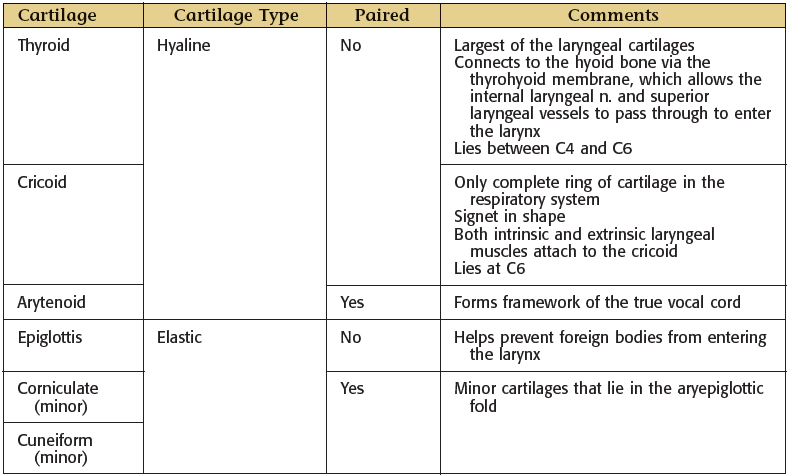

Larynx